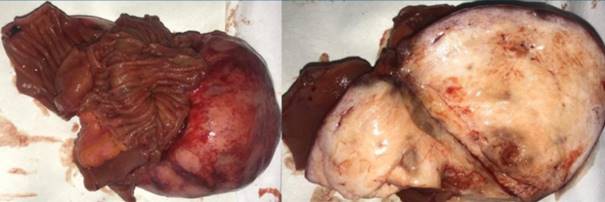

Biopsia extemporánea: tumoración blanquecina, sólida, lisa, de 70 x 35 x 45 mm sin invasión de la mucosa intestinal. Proliferación de tipo fusocelular (figura 2). Buena evolución clínica. Alta al 5º día posoperatorio.

Figura 2: Anatomía patológica.Macroscopía: tumoración de 70 x 35 x 45 mm, sólida, lisa, blanquecina, adherida al intestino delgado. Al corte no presenta invasión del asa